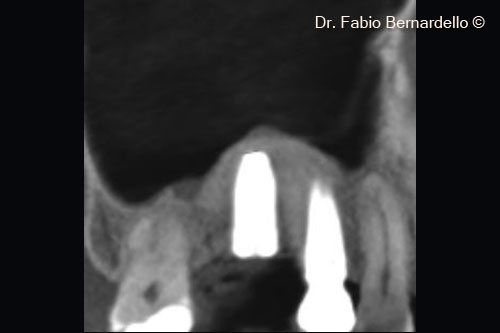

Ảnh chụp X-Quang trước phẫu thuật. Một trụ Implant đã được cấy ghép để thay thế răng số 16 khoảng 10 năm trước

Cấu trúc xoang hẹp ( Chiều rộng < 12mm khi đo ở vị trí cách sống hàm trên 10mm) chiều cao xương còn lại từ 3 mm đến 5 mm cho phép thực hiện phẫu thuật 1 thì. Nâng xoang hàm và cấy ghép implant theo vị trí.